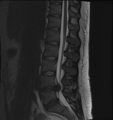

MRI scan of cervical disc herniation between sixth and seventh cervical vertebral bodies.

- Magnetic resonance imaging (MRI): A diagnostic test that produces three-dimensional images of body structures using powerful magnets and computer technology. It can show the spinal cord, nerve roots, and surrounding areas, as well as enlargement, degeneration, and tumors. It shows soft tissues even better than CAT scans. An MRI performed with a high magnetic field strength usually provides the most conclusive evidence for diagnosis of a disc herniation. T2-weighted images allow for clear visualization of protruded disc material in the spinal canal.